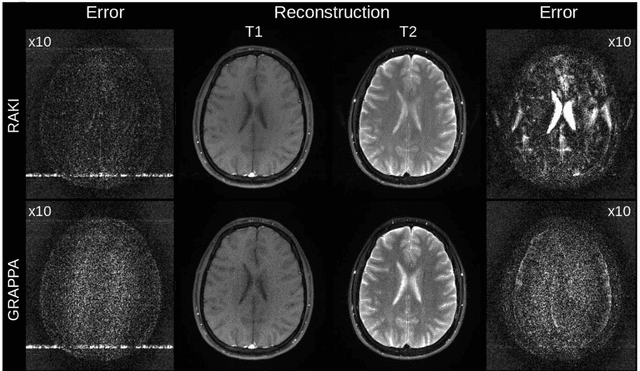

Abstract:MRI scan time reduction is commonly achieved by Parallel Imaging methods, typically based on uniform undersampling of the inverse image space (a.k.a. k-space) and simultaneous signal reception with multiple receiver coils. The GRAPPA method interpolates missing k-space signals by linear combination of adjacent, acquired signals across all coils, and can be described by a convolution in k-space. Recently, a more generalized method called RAKI was introduced. RAKI is a deep-learning method that generalizes GRAPPA with additional convolution layers, on which a non-linear activation function is applied. This enables non-linear estimation of missing signals by convolutional neural networks. In analogy to GRAPPA, the convolution kernels in RAKI are trained using scan-specific training samples obtained from auto-calibration-signals (ACS). RAKI provides superior reconstruction quality compared to GRAPPA, however, often requires much more ACS due to its increased number of unknown parameters. In order to overcome this limitation, this study investigates the influence of training data on the reconstruction quality for standard 2D imaging, with particular focus on its amount and contrast information. Furthermore, an iterative k-space interpolation approach (iRAKI) is evaluated, which includes training data augmentation via an initial GRAPPA reconstruction, and refinement of convolution filters by iterative training. Using only 18, 20 and 25 ACS lines (8%), iRAKI outperforms RAKI by suppressing residual artefacts occurring at accelerations factors R=4 and R=5, and yields strong noise suppression in comparison to GRAPPA, underlined by quantitative quality metrics. Combination with a phase-constraint yields further improvement. Additionally, iRAKI shows better performance than GRAPPA and RAKI in case of pre-scan calibration and strongly varying contrast between training- and undersampled data.